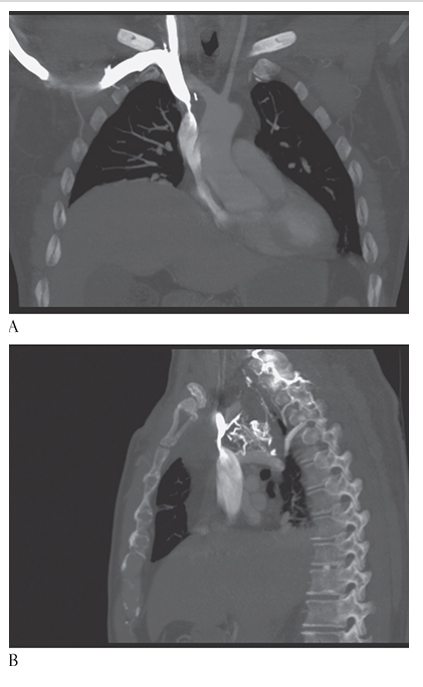

What is A

Superior Vena Cava Syndrome. CECT coronal and MPR CECT sagittal

What is B

Superior Vena Cava Syndrome. CECT coronal images show significant narrowing of the superior vena cava with development of multiple collaterals.